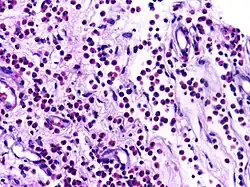

Dysgerminoma | Dysgerminoma characterized by uniform cells resembling primordial germ cells separated by fibrous septa with lymphocytes. | Category: Histopathology of ovarian dysgerminoma | Ovarian dysgerminoma |

![]() |